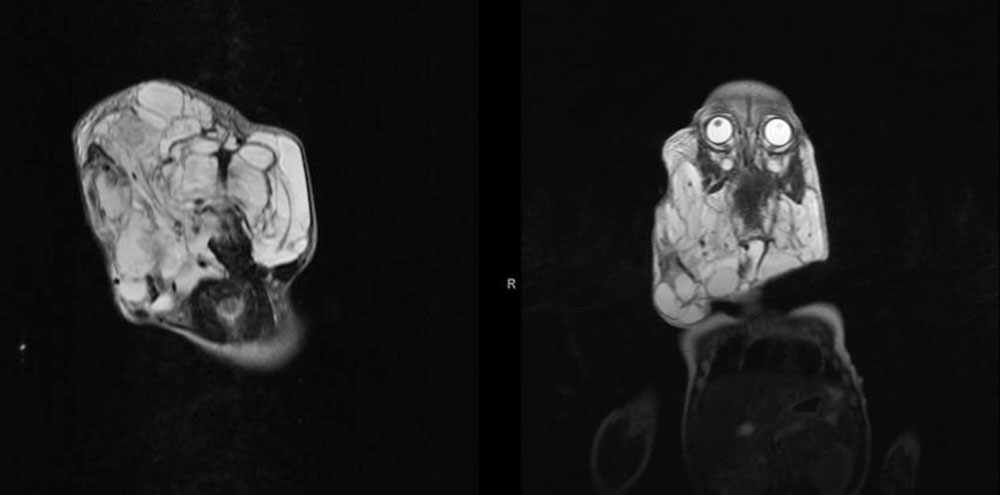

In the thigh, a lymphatic malformation can develop between muscle groups and cause displacement, usually without symptoms. An LM in the floor of the mouth between and within the numerous small muscles of the tongue often gives the impression of diffuse infiltration and macroglossia.